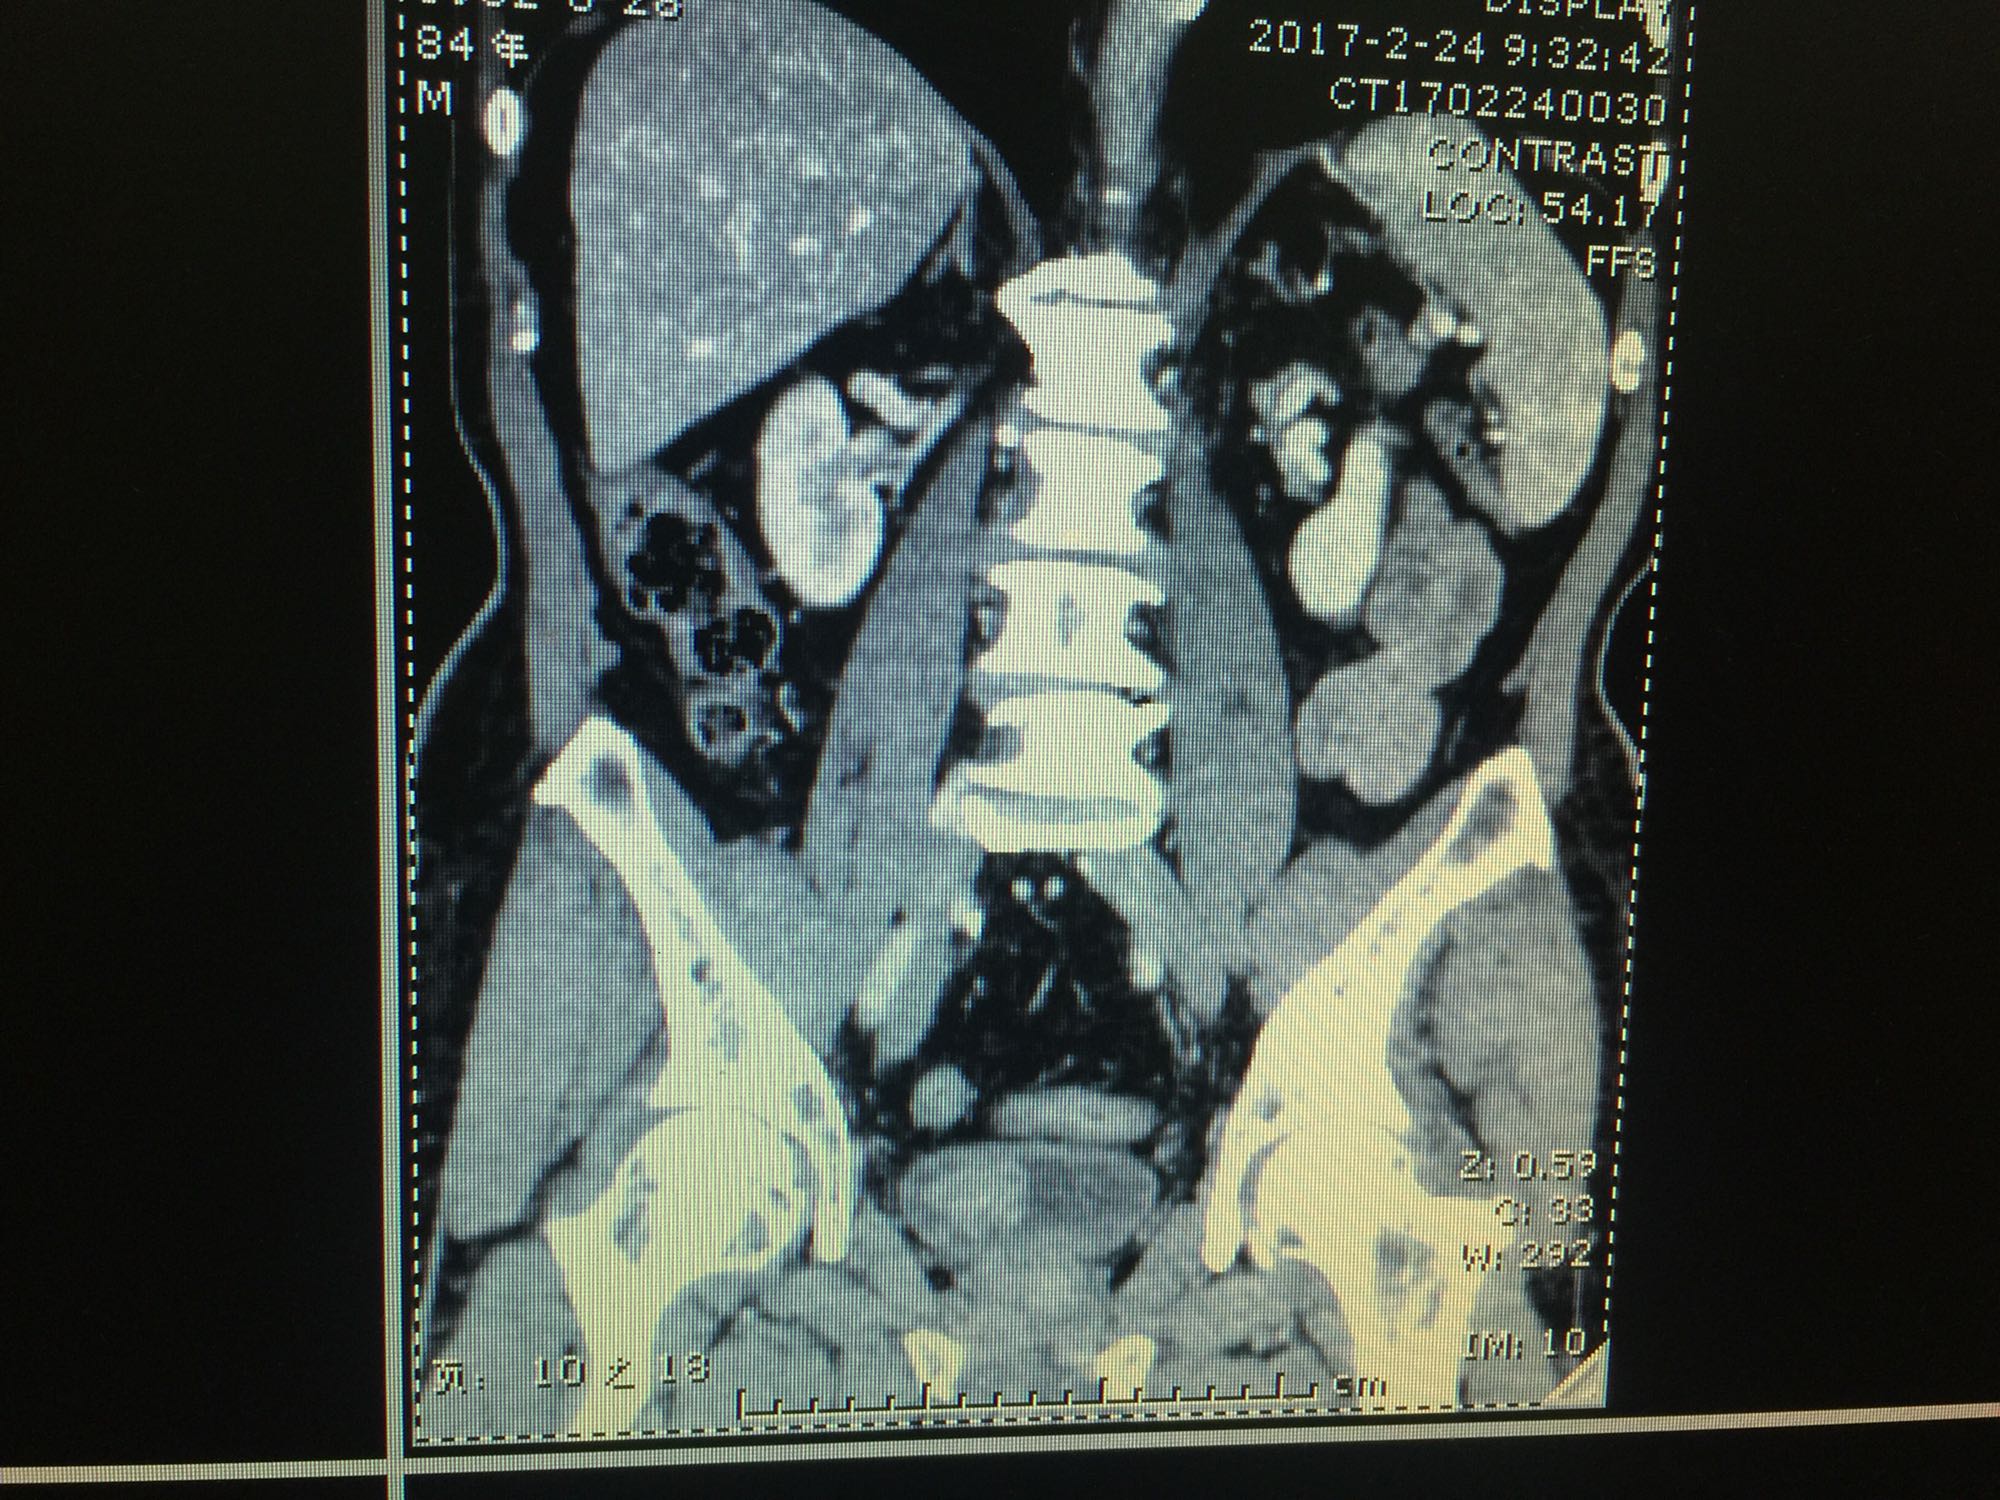

膀胱占位一例

膀胱癌

80岁男性 既往冠心病 血尿3月,发现膀胱新生物2天入院

予以膀胱肿瘤电切 术后冲洗清亮,但到夜间冲洗鲜红色,血压正常,术中前列腺充血不明显。予以止血对症治疗后,转为清亮,出血时间约6小时。但血色素从144降到126 。

膀胱肿瘤术后出血,常为止血不彻底,合并前列腺出血或者血压等波动造成。 还有哪些因素可以导致膀胱肿瘤术后出血而自止了呢?